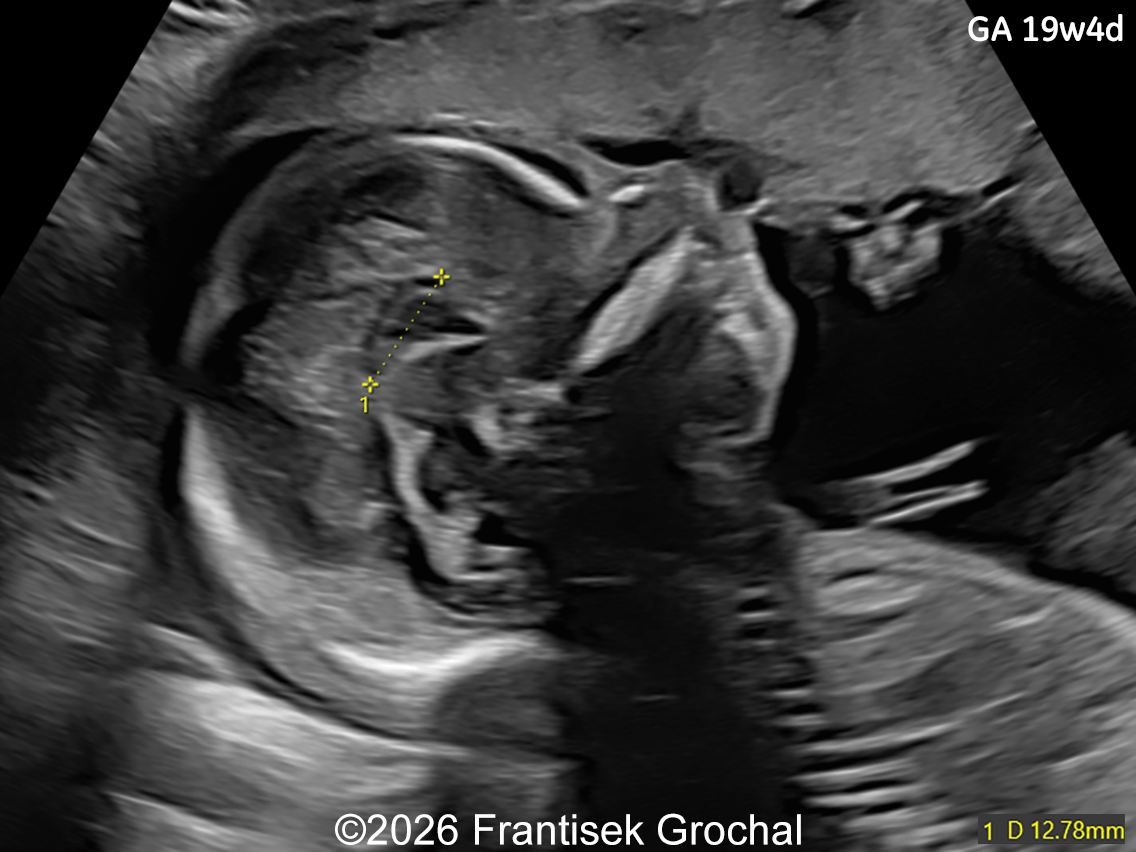

Image 4

• Micrognathia

19+4 weeks of gestation; sagittal view of the fetal head demonstrating prefrontal edema, nasal bone hypoplasia, retrognathia, and a short corpus callosum.

Image 1 19+4 weeks of gestation; sagittal view of the fetal head demonstrating prefrontal edema, nasal bone hypoplasia, retrognathia, and a short corpus callosum.